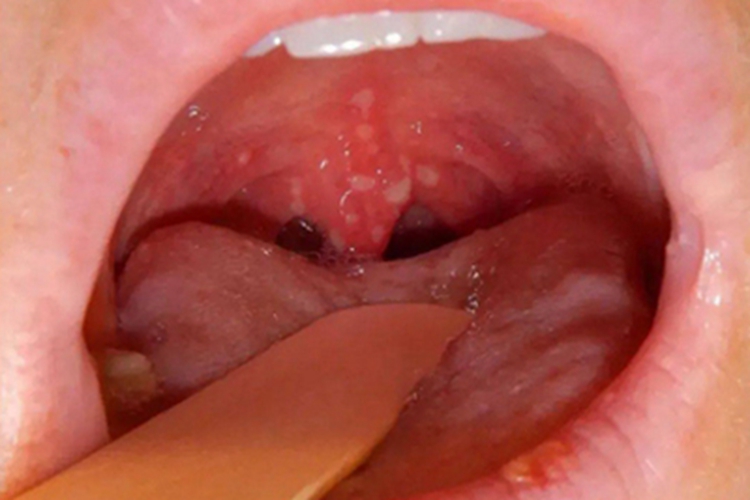

咽喉疱疹表现为咽喉部散在数量不等的灰白色小疱疹,直径1-2mm,周边有红晕,疱疹之间可融合成片,逐步破溃呈黄色溃疡。同时患者可伴有发热、咽痛等症状。